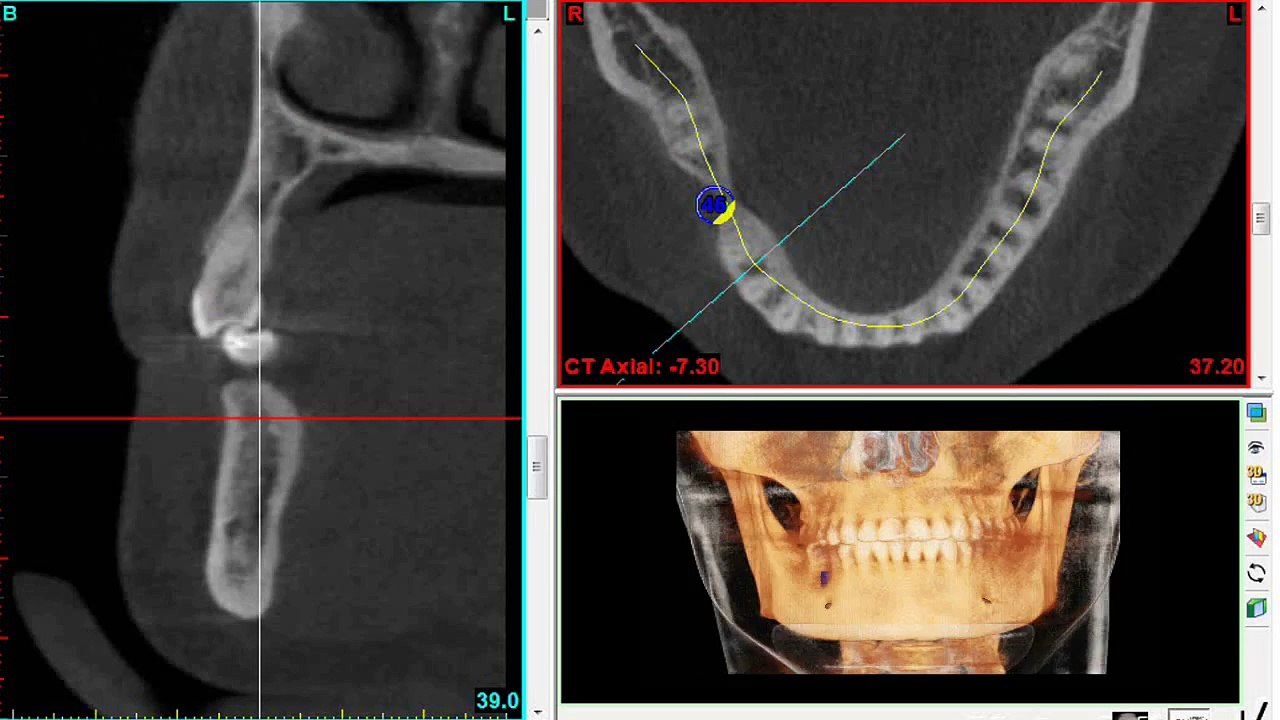

üst çene implant uygulamalarında sinus lifting